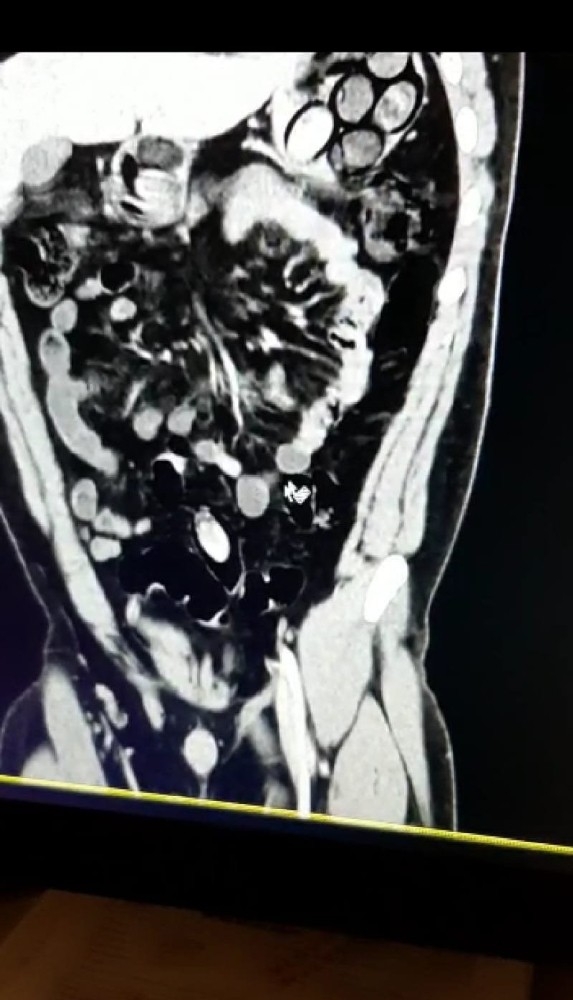

Antalya Cumhuriyet Başsavcılığı koordinesinde, Narkotik Suçlarla Mücadele Şube Müdürlüğü Narkotik Suçlarla Mücadele Hudut Büro Amirliği görevlilerince Antalya Havalimanı'nı kullanarak diğer illerden ve ülkelerden uyuşturucu madde nakli yapan şahıs ve gruplara yönelik çalışmalar devam ediyor. Son olarak Antalya'ya gelen bir uçağın yolcuları arasında bulunan, şüpheli ve tedirgin davranışlar sergileyen, İran uyruklu B.P. isimli şahıs durduruldu. Zanlının uyuşturucu madde kuryelerinden olabileceği ve yutmak suretiyle bağırsaklarında ve midesinde uyuşturucu getirebileceği değerlendirildi. Yapılan kontrolde şahsın mide ve bağırsaklarında 45 adet kapsül 765 gram eroin olduğu anlaşıldı.